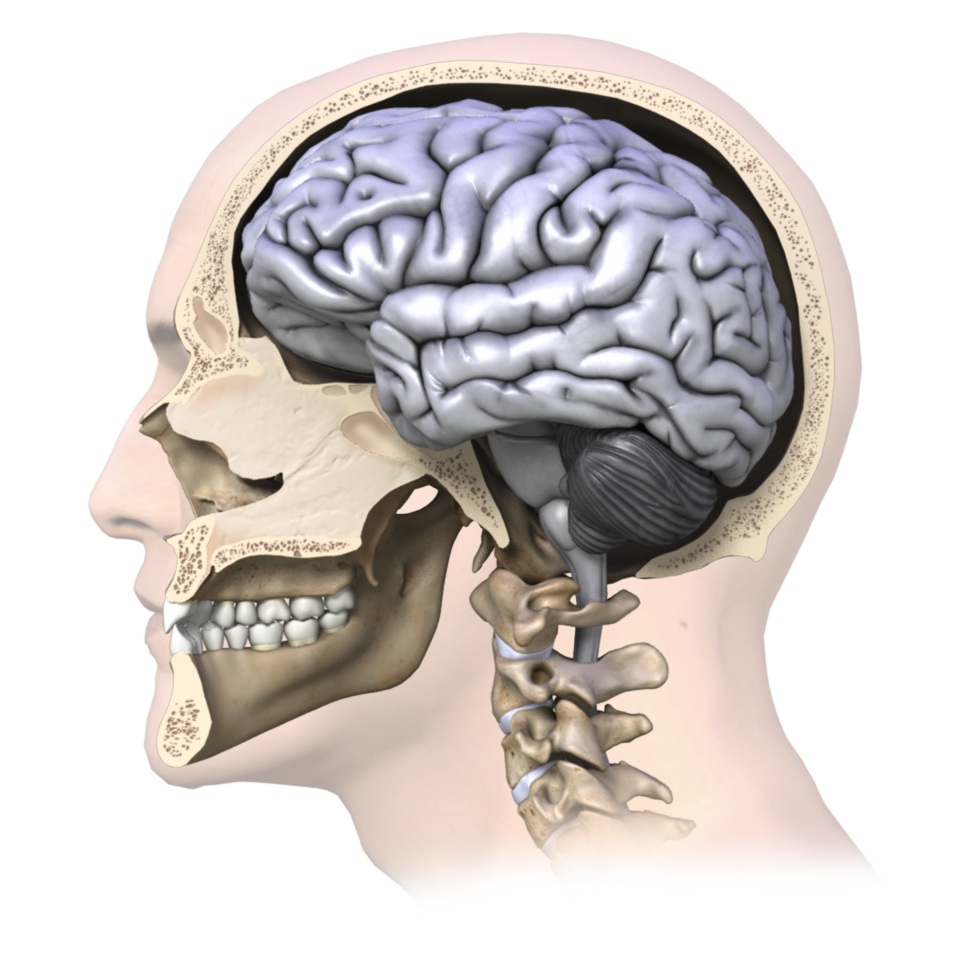

Although you wouldn’t know it from the outside, the human head is made up of 22 bones, which includes that of the mandible (better known as the jaw). These 22 bones not only encase the most important structure to our conscious being, the brain, but they also create the solid framework for important sensory structures such as the eyes and ears. Injuries involving the head could mean injury to the brain or other vital structures of the head and should be considered serious.